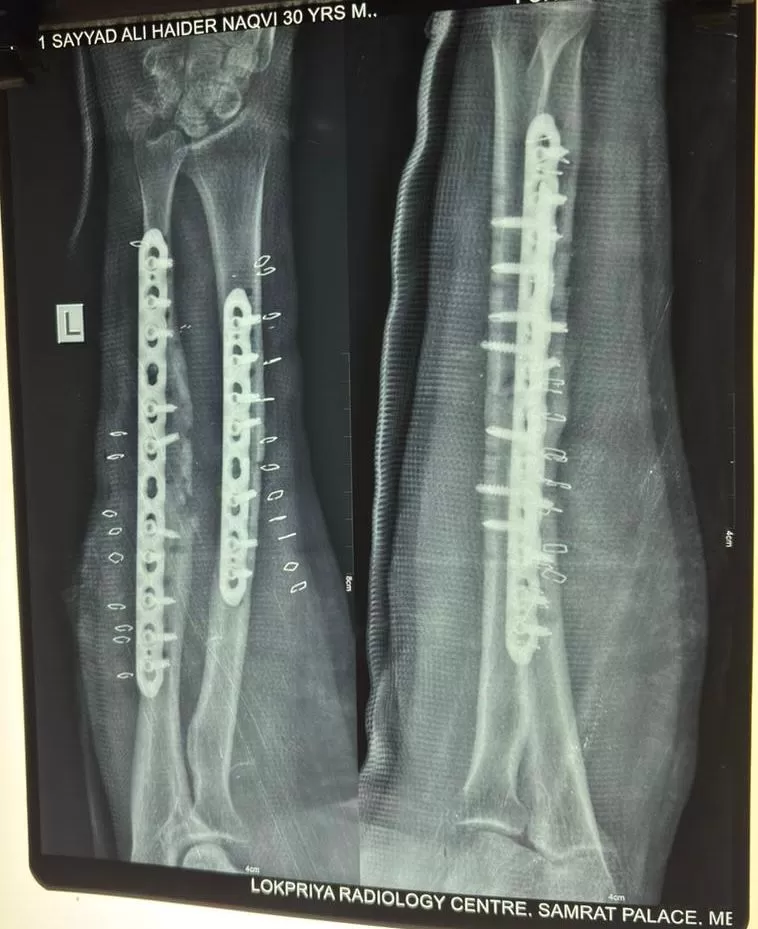

Mr. Haider

Name: Mr. Haider

Date of Operation: 28 September

Age: 27 Years